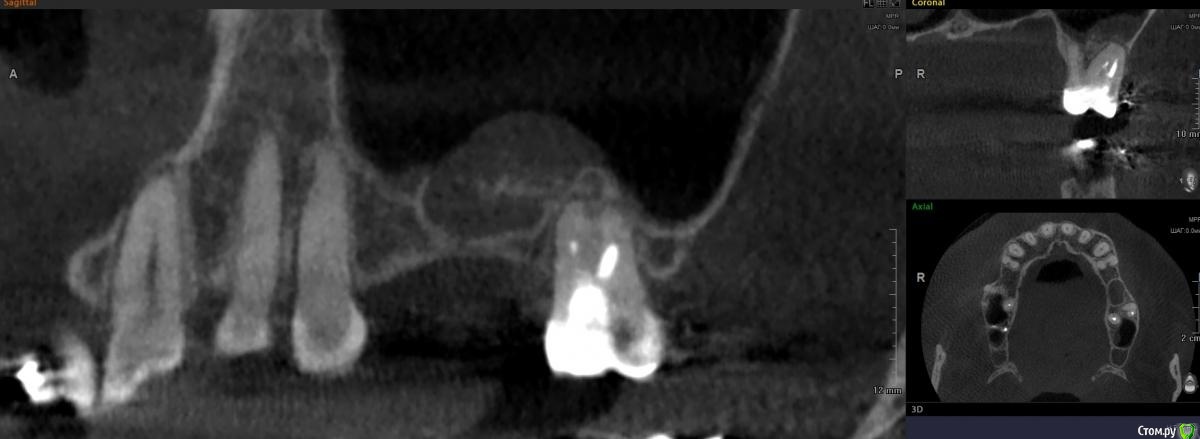

dr.Dre Опубликовано 4 августа, 2020 Поделиться Опубликовано 4 августа, 2020 Добрый день коллеги ,планируеться синус,ничего не беспокоит .Убирать самому или ,направить к лору как думаете ? Ссылка на комментарий

Дмитрий Л. Опубликовано 4 августа, 2020 Поделиться Опубликовано 4 августа, 2020 Неплохое кт, это планмека? Либо 4 мм имплант тишью левел, не затрагивая гайморову, либо открытый синус с croco eye. Ссылка на комментарий

колесников Опубликовано 5 августа, 2020 Поделиться Опубликовано 5 августа, 2020 Вообще не трогайте. Вы что Д’Артаньян ? Очень толстая стенка синуса,сделайте закрытый синус. Киста или сама лопнет или пациент к Лору обратится если что то забеспокоит. Качество кости не смущает? Что за пациент? Как выглядит костная ткань на н/ч? Эмаль не изменена? Сопутствующие патологии имеются? Ссылка на комментарий

Kilgen Опубликовано 24 августа, 2020 Поделиться Опубликовано 24 августа, 2020 Закрытый с.л + т.л 6 мм Ссылка на комментарий

Александр07 Опубликовано 30 августа, 2020 Поделиться Опубликовано 30 августа, 2020 Неплохое кт, это планмека? Либо 4 мм имплант тишью левел, не затрагивая гайморову, либо открытый синус с croco eye.Если мануал высокий и уверенность и опыт есть в закрытии перфорации то пошёл бы по ядаху но там высокий риск образования большой перфы, поэтому хорошая альтернатива это короткие широкие импл и закрытый с л Ссылка на комментарий

Snow Doc Опубликовано 1 сентября, 2020 Поделиться Опубликовано 1 сентября, 2020 Плюсую к 6мм Тл. Ещё и септа неприятная, по всей видимости, для открытого. Ссылка на комментарий